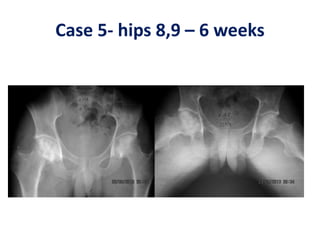

Case 5- hips 8,9 – 6 weeks

Case 5- hips8,9 – 6 weeks